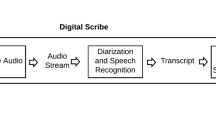

Challenges of developing a digital scribe to reduce clinical documentation burden

Juan C. Quiroz, Liliana Laranjo, … Enrico Coiera

The digital scribe in clinical practice: a scoping review and research agenda

Marieke M. van Buchem, Hileen Boosman, … Ewout W. Steyerberg

Assessing the accuracy of automatic speech recognition for psychotherapy

Adam S. Miner, Albert Haque, … Nigam H. Shah